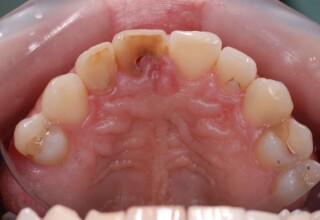

Dark root canal teeth

A rare case of dark root canal teeth with additional external absorption on the central incisor. After removal of the affected tissues of the central incisor, the tooth could not be directly bleached because of the soft tissue contact. The tooth was initially restored to provide the original tooth form, then it was bleached and the restoration was finalized.

Initial appearance

Final appearance